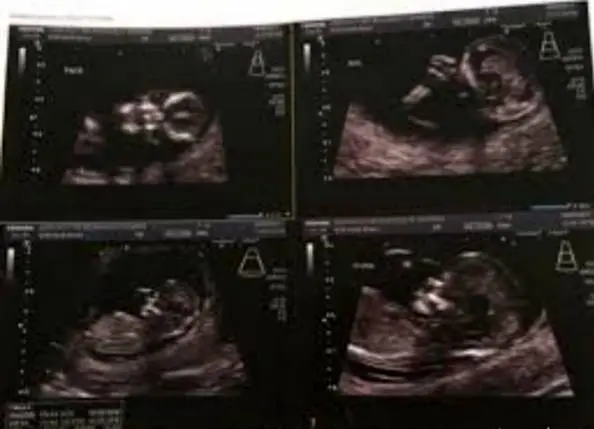

عکس به اشتراک گذاشته شده که در این بخش مشاهده می کنید جنین را به شکل یک جمجمه عجیب انسان نشان می دهد ، حالتی واقعا ترسناک و شوکه کننده که با واکنش های منفی بسیاری روبرو شد اما مادر جوان اعلام کرده است که قصد سقط جنین ندارد و او را تا ماه نهم در شکم خود نگاه خواهد داشت.